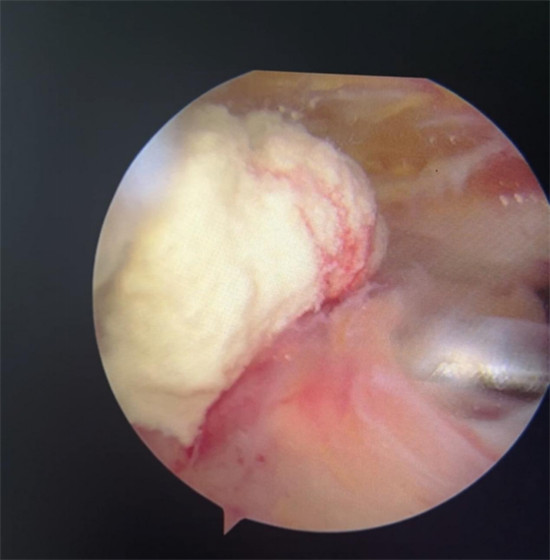

賀大媽慕名來(lái)廣安醫(yī)院找羅軍主任就診,面對(duì)羅醫(yī)生,賀大媽哭訴:“羅醫(yī)生,我真想剁下自己的這只胳膊。”羅軍主任根據(jù)患者的癥狀拍片,診斷為岡上肌鈣化性肌腱炎,隨后,羅醫(yī)生為李大媽進(jìn)行了肩關(guān)節(jié)鏡微創(chuàng)手術(shù),竟從她的右肩“擠”出“牙膏”。

鈣化性肌腱炎是一種自限性疾病,就是疾病發(fā)生發(fā)展到一定程度后,經(jīng)長(zhǎng)期機(jī)體調(diào)節(jié)能夠控制病情發(fā)展并逐漸恢復(fù)痊愈。它分為四個(gè)階段:鈣化前期、鈣化形成期、鈣化吸收期、鈣化后期,往往在“鈣鹽斑塊”吸收時(shí),疼痛最劇烈,賀大媽就正處于“吸收期”。

是不是只要病人撐得住,讓鈣鹽吸收就沒(méi)事了?羅軍主任表示,經(jīng)保守治療無(wú)法緩解或病程長(zhǎng)的患者,應(yīng)盡早采取手術(shù)治療。而且,部分患者鈣鹽無(wú)法完全吸收,拖下去只會(huì)使病情惡化,造成肩膀肩袖肌腱的損傷。